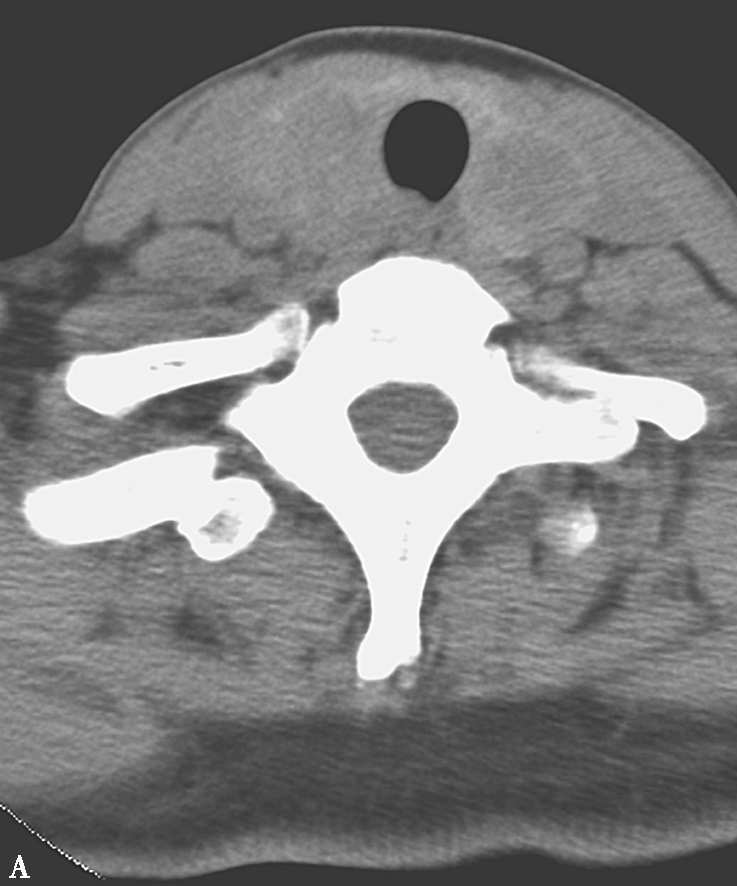

缺碘引起的弥漫性甲状腺肿大若未经及时治疗,病变发展可使扩张的滤泡集成多个大小不等的结节,逐渐形成结节性甲状腺肿。临床症状主要是肿大的结节增大后,压迫气管、食管和血管,引起呼吸困难、吞咽障碍和头面血液回流障碍的表现。CT和MRI检查都对结节性甲状腺肿大的诊断有重要价值,但相比而言,MR检查目前应用不如CT普及。CT平扫甲状腺弥漫性肿大,包膜完整,腺体表面隆起可呈浅分叶状。增大甲状腺可见多个大小不等低密度结节(图2-14A)。结节边缘可见弧样或粗斑点状钙化,增强扫描结节呈不同形式、不同程度的强化(图2-14B)。

图2-14 多结节性甲状腺肿

A.CT平扫横轴位;B.增强扫描,示双侧甲状腺增大,边缘规则,内可见多个散在的低密度结节,增强后结节呈不均匀强化